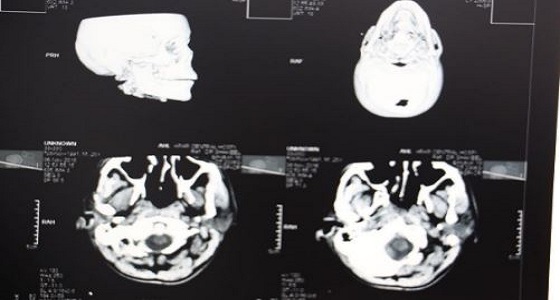

إنقاذ حياة مريض أصيب بكسور الجمجمة بمستشفى بريدة

منذ 1 سنة

1

2614